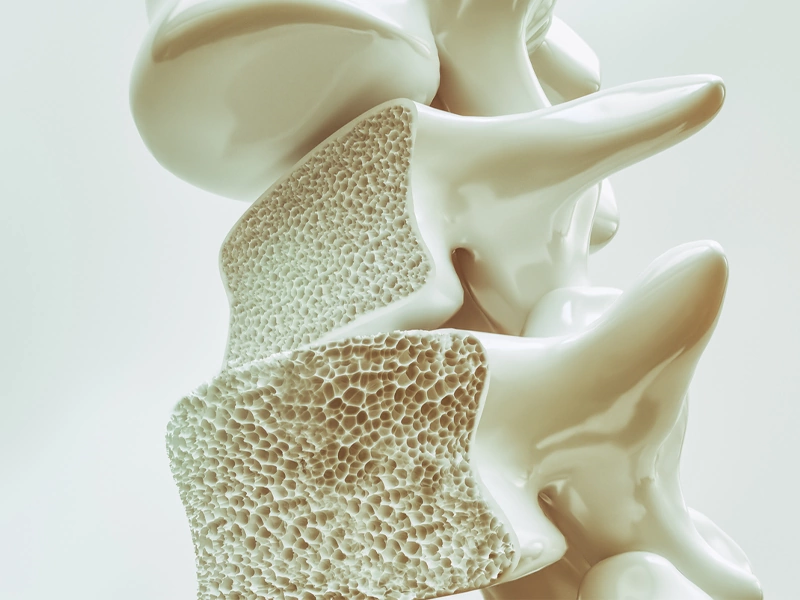

پوکی استخوان یک اختلال اسکلتی است که بیشتر در سنین بالا بروز میکند و ویژگی آن کاهش استحکام استخوان هاست. این بیماری به تدریج و